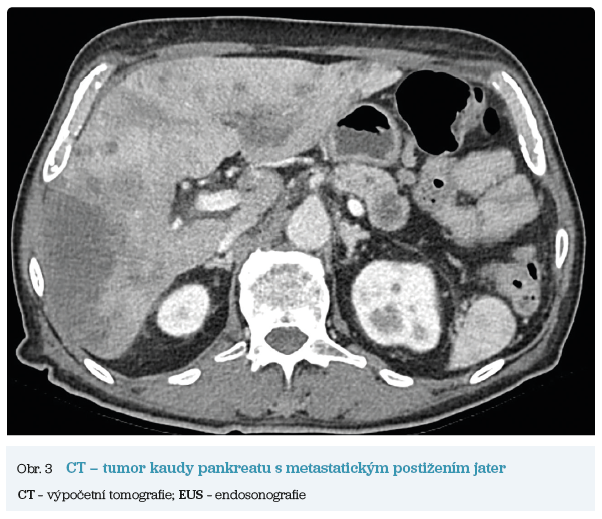

Několik studií se zabývalo AI asistovanou CT detekcí karcinomu pankreatu s AUC 0,79–0,99 %,6–8 tedy přesností porovnatelnou s přesností práce zkušeného radiologa. Stran časné detekce proběhla studie posuzující přesnost AI modelu v detekci karcinomu pankreatu v období 3–36 měsíců před prvními projevy onemocnění. Zařazeno bylo 155 pacientů s karcinomem pankreatu a 265 zdravých kontrol. AI model zde dosáhl AUC 0,98, což výrazně předčilo radiology, kteří při popisování stejných případů dosáhli AUC 0,66.9 Studie využívající DL model pro rozlišení zdravé slinivky od nálezu pankreatických neoplazií, tedy karcinomu pankreatu, intraduktální papilární mucinózní neoplazie (IPMN), serózních a mucinózních cystických neoplazií a solidní pseudopapilární neoplazie, byla prezentována s AUC 0,91, tedy opět odpovídající přesnosti popisu radiologa.10 Pro další vývoj a možné klinické využití bude potřeba přístupu k rozsáhlému archivu CT snímků karcinomu pankreatu, aby se ML modely mohly zdokonalovat. Další studie se věnovaly AI asistované diferenciální diagnostice. Ta bývá u lézí pankreatu velmi obtížná a pokrok v této problematice je tak velmi přínosný. Mezi nejzajímavější patří studie zabývající se rozlišením serózních a mucinózních cystadenomů s AUC 0,932.11 Další studie zkoumala úspěšnost rozlišení karcinomu pankreatu od zbytnění pankreatu při určitých formách chronické pankreatitidy (MFP – mass forming pancreatitis) s AUC 0,866.12 V další studii byla AI využita k rozlišení fokální autoimunitní pankreatitidy od karcinomu pankreatu s AUC 0,97.13 V rámci MR proběhlo několik studií, které se zaměřily na AI asistované zachycení a klasifikaci pankreatického karcinomu či IPMN. Studie klasifikující IPMN pomocí konvoluční neuronové sítě (CNN – convolutional neural network) byla schopna rozlišit dysplazii vysokého stupně od přítomnosti karcinomu se senzitivitou 76 %, specificitou 78 % a AUC 0,78.14 Další studie porovnávala AI modely CT a MR v predikci maligního IPMN. Výsledky ukázaly, že MR model s AUC 0,94 byl přesnější než CT model s AUC 0,864.15 S využitím PET/CT byl prozkoumán AI model rozlišující od sebe akutní pankreatitidu a karcinom pankreatu s AUC 0,9668.16 Výsledky AI v oblastech zobrazovacích metod jsou tak slibné. Dosahují minimálně přesnosti srovnatelné s radiologem a zejména v problematice časných karcinomů pankreatu člověka svojí přesností převyšují (obr. 1–5).